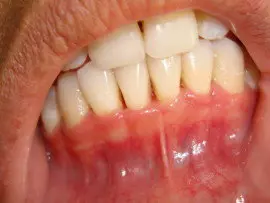

Some symptoms of periodontitis includes bleeding gums, bad breath, increased sensitivity to heat & cold and in later stages pain, swelling, pus discharge & mobility of teeth.

Gum swelling that recurs

Gingival recession, resulting in apparent lengthening of teeth